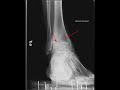

This is a patient who presents with chronic ankle pain. Frontal and lateral radiographs of the ankle were obtained. The red arrows on the frontal radiograph demonstrate severe narrowing of the tibiotalar joint space. There is subchondral sclerosis, osteophyte formation, and large subchondral cyst formation indicative of advanced osteoarthritis. The lateral radiograph demonstrates similar findings. However, the ankle is a joint which is not typically associated with severe secondary osteoarthritis unless there is a predisposing disease condition or event. Differential considerations would include severe secondary osteoarthritis due to trauma, septic arthritis, neurogenic arthropathy, or hemophilia. The diagnosis in this case is hemophilic arthropathy. Hemophilia occurs in male patients who get recurrent hemarthroses which eventually leads to severe secondary osteoarthritis.